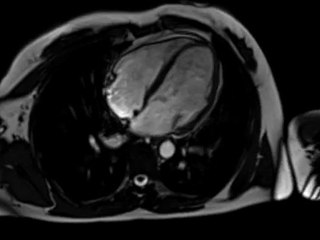

Sites websblogs, copiez cette vidéo avec le bouton "code embed" ! Si vous voulez télécharger, allez sur . Le nouveau centre d'imagerie de médecine nucléaire installé dans l'infirmerie protestante de Caluire, a été inaugurée. Plus sur .